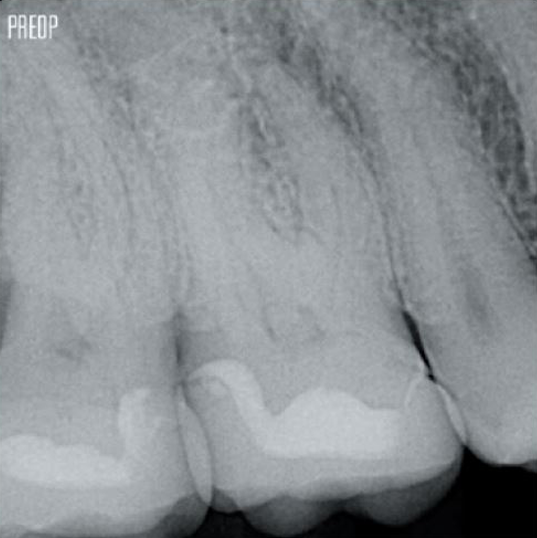

Photos avec l’aimable autorisation du Dr Ahmed Salman

Une cavité d’accès endodontique conservatrice (CEC) est recommandée avec le système TruNatomy®.

L’accès est désormais possible sous différents angles alors que, jusqu’à présent, il fallait sacrifier la structure (cavité endodontique traditionnelle).1

Plus besoin d’un accès en ligne droite.1

L’union de la géométrie de la lime, des conicités régressives et du fil mince et très flexible permet un traitement efficace du canal radiculaire tout en n’enlevant la dentine que là où c’est cliniquement nécessaire.1